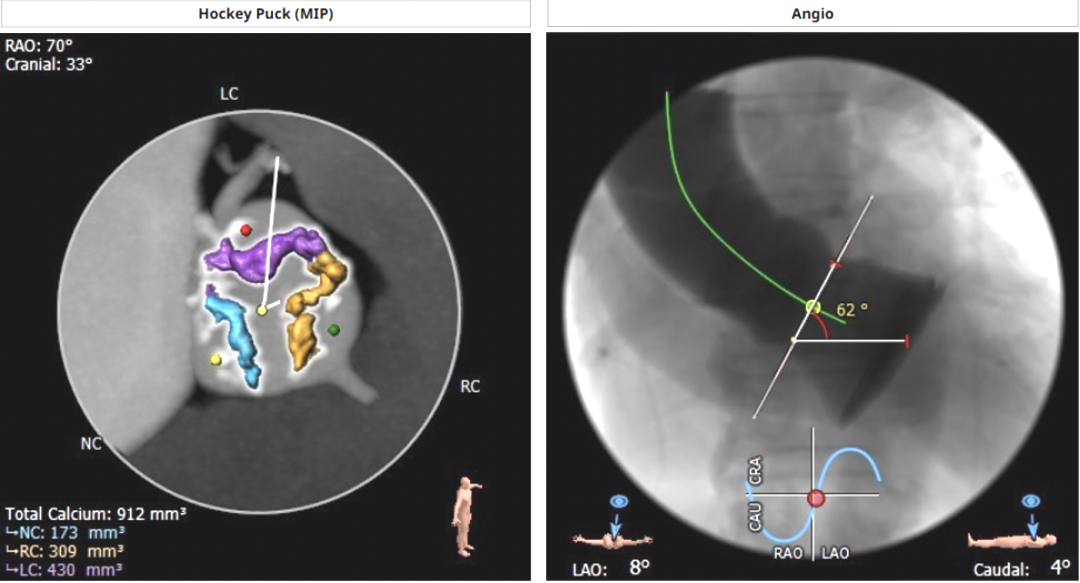

钙化积分912mm³,重度钙化;心脏角度:62°